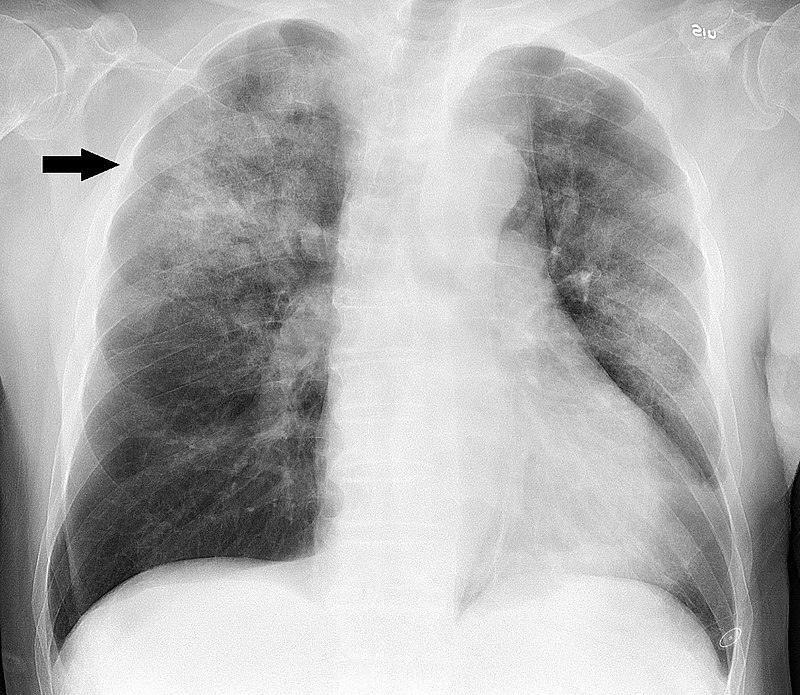

What will you see in a CXR that you requested in sus Bronchitis but you acc sus Pneumonia?

If bronchitis = normal CXR

If pneumonia = consolidation